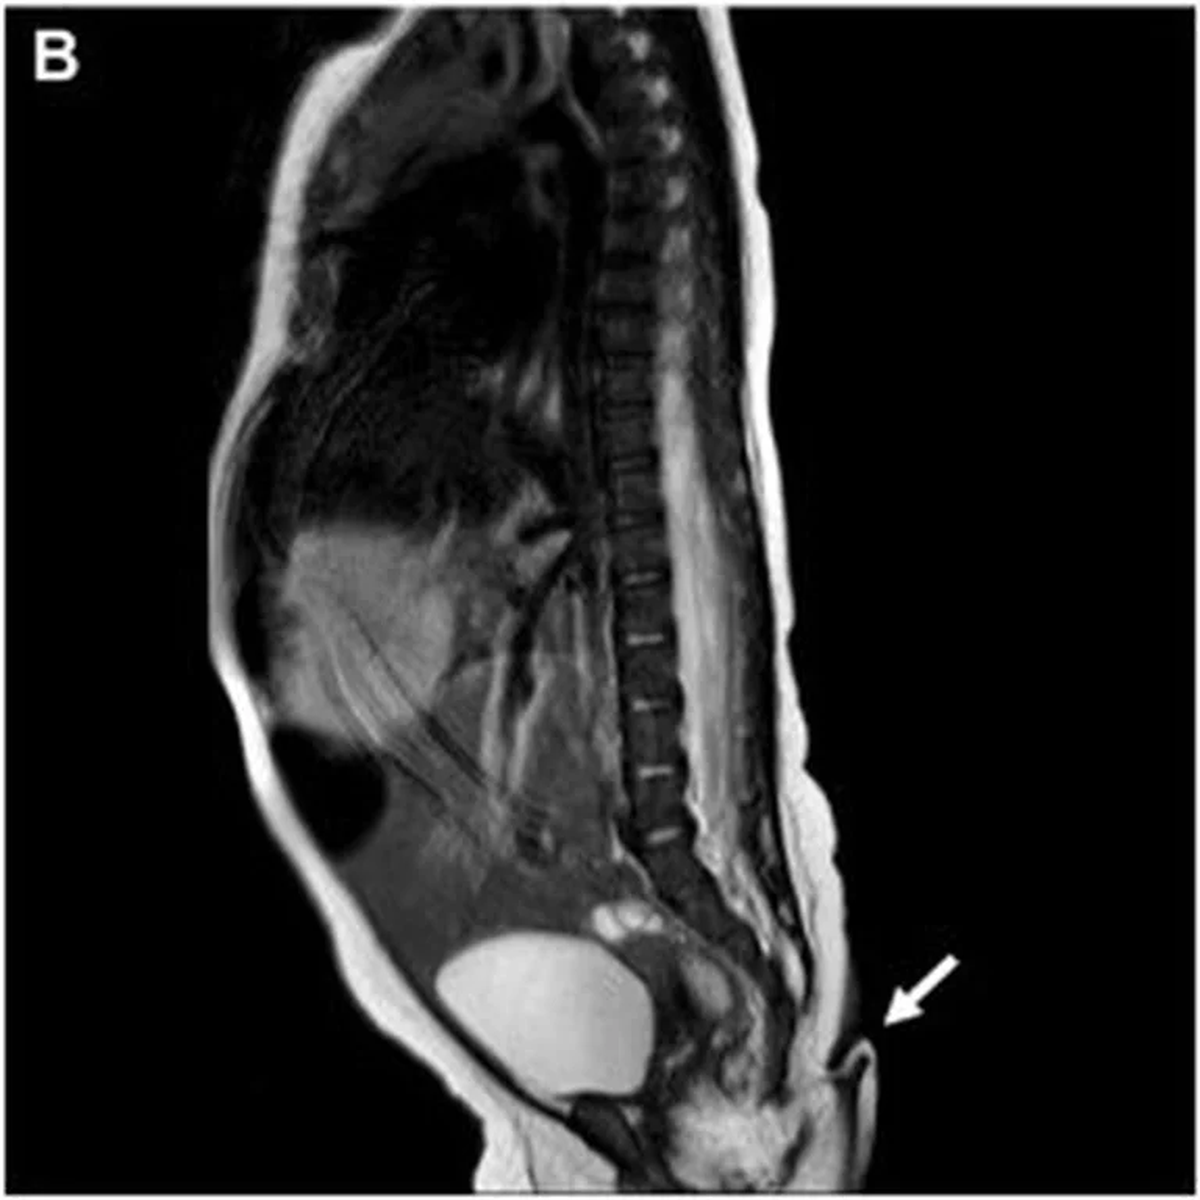

Asimismo, la resonancia magnética practicada no reveló anormalidades cerebrales, además, fue negativa para disrafismo posterior, y presentó médula espinal y cono medular de características normales. Entre tanto, la exploración auditiva y cardíaca fue normal, es decir: una bebé sana, por lo que fue dada de alta para seguimiento ambulatorio.